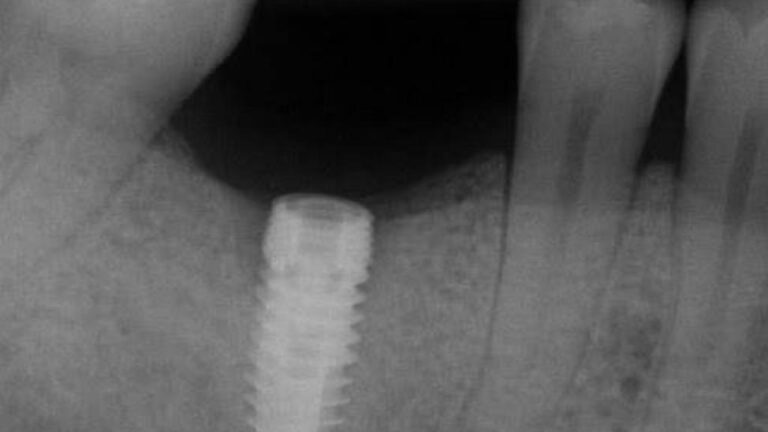

The patient presented on referral for retrieval of a fractured abutment from a 4.8 Straumann BL RC implant in the #18 site.